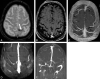

Fig 4.

Fifty-three-year-old man with chronic left lateral sinus thrombosis (thrombus age approximately 7 years). Combo-4D MRV consisting of dynamic 3D contrast-enhanced MR venographic images and static 3D contrast-enhanced VIBE MR venographic images. Upper panel, Coronal MIP reformations of combo-4D MRV demonstrate chronic thrombosis of the left lateral sinus. On early venous phase image of the dynamic MRV series (A), a thin channel of contrast enhancement is depicted within a large gap inside the left transverse/sigmoid sinus (long arrow). An increase in this contrast enhancement is noted at the subsequent later venous phase (time delay of 1.5 seconds between dynamic images) on the corresponding image (long arrow, B). On the static MRV image (C), intense contrast-enhancement mimicking patency of these sinuses is disclosed (long arrow). Note also focal postthrombotic changes inside the right lateral sinus (short arrows) without dynamic contrast enhancement. Middle panel, Targeted axial oblique MIP reformations (parallel to the course of the lateral sinuses) of combo-4D MRV show more clearly the dynamic enhancement patterns of chronic left lateral sinus thrombosis (D–F). Lower panel: On corresponding axial GRE image, no relevant magnetic susceptibility effect is observed in the affected venous sinuses (G; short arrow and arrowheads). On T2W image, chronic thrombus reveals an isointense signal intensity (H; short arrow and arrowheads). Complete loss of normal flow signal intensity in left lateral sinus and jugular bulb, as well as irregular signal intensity void at the right transverse/sigmoid sinus junction are depicted on coronal MIP reformation of 2D-TOF MRV (I).